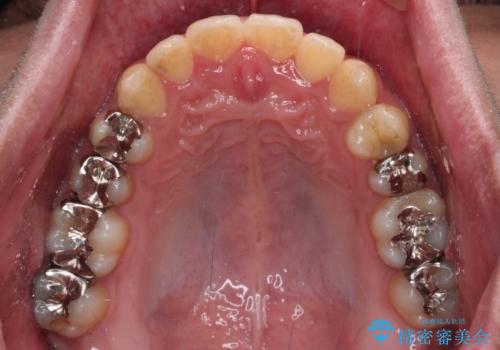

前歯のクロスバイト インビザラインによる矯正治療

- 上下のクロスバイトと前歯のデコボコを気にして来院された患者様です。

インビザラインを用い、IPR(歯と歯の間を削る)と歯列全体を拡大させることで、歯並びを整えていくこととしました。

インビザライン特有の、治療後半に奥歯が咬み合わないという事象が長引きました。

咬み合わないときの対処方法は色々とありますが、ゴムかけなどを活用して噛めるようにしました。